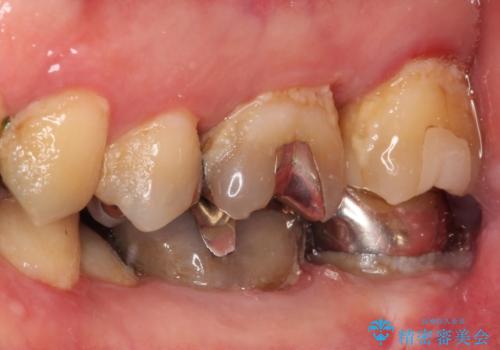

- 奥歯に食べ物がよくはさまるのが気になるとのことで来院された患者様です。

フロスをすると第一大臼歯の部分が引っ掛かり段差になっていることがわかりました。

インレーの範囲が大きいためオールセラミッククランにて補綴することとしました。